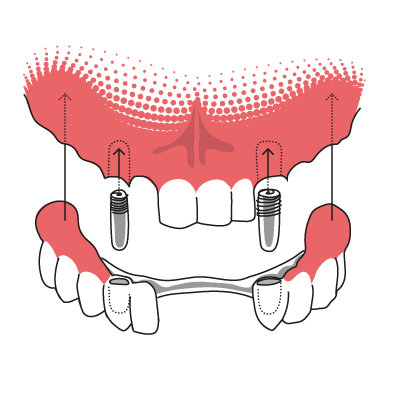

Implantat-Teleskopprothese